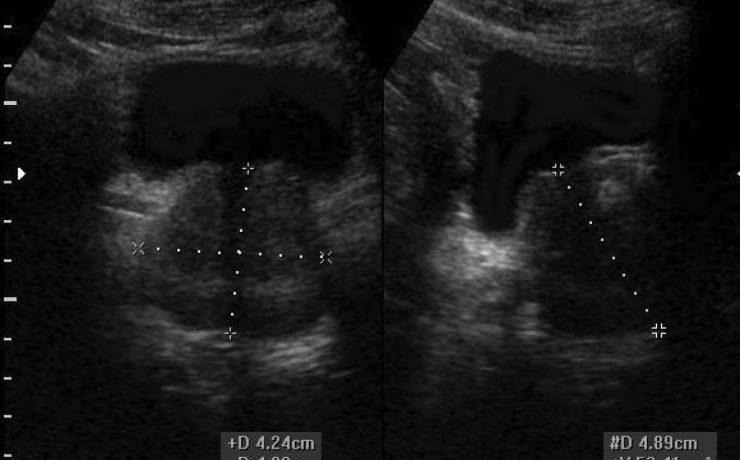

Se realizó un estudio descriptivo prospective, evaluando a 336 pacientes operados de colecistitis aguda o crónica por vía laparoscópica. Todos los pacientes fueron evaluados con ecografía abdominal al menos 7 días antes de la cirugía por un médico radiólogo experto y de acuerdo a varios parámetros se dividen en 3